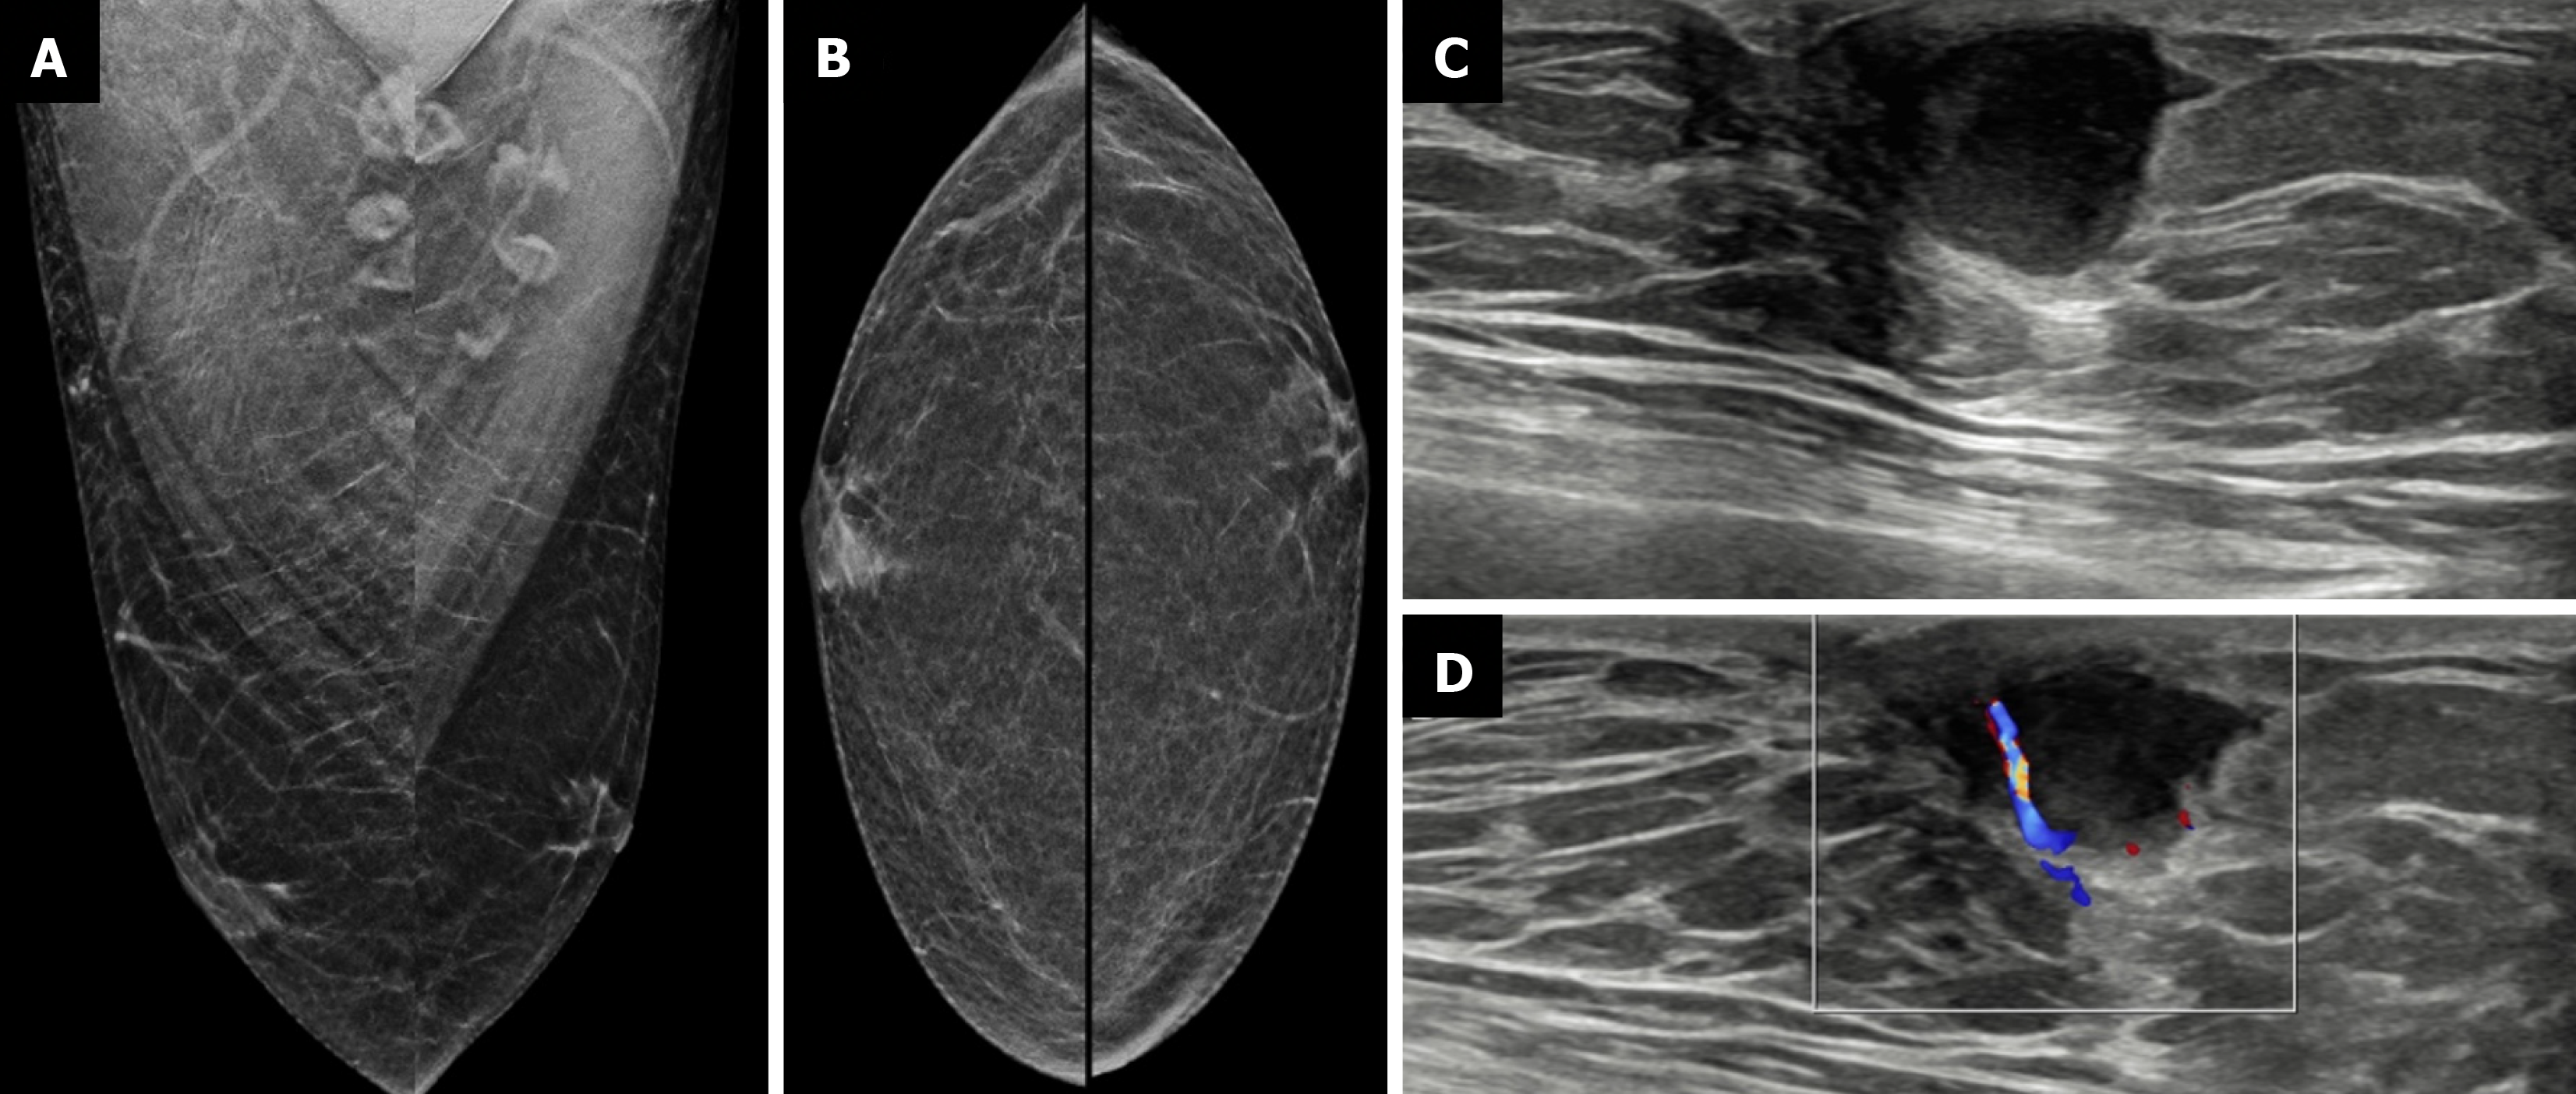

Figure 10  Infective collection from a 23-year-old male with a history of high-grade fever after trauma to the left breast.

A: Mediolateral oblique; B: Craniocaudal mammography views showing no obvious abnormality; C: Ultrasound; D: Color Doppler images revealing a well-defined anechoic collection with peripheral internal vascularity.